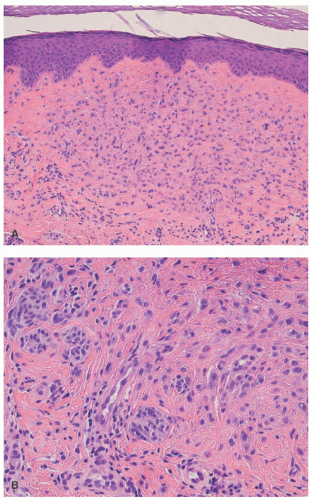

Atypical melanocytic nevus is a generic category based in part upon the clinical appearance and the pathologic features of the nevocellular proliferation. An irregular distribution of junctional nests, lentiginous (single-cell) junctional pattern, and nuclear alterations such as enlargement, density and coarseness of the chromatin, prominence of the nucleoli and mitotic figures, and their location are some of the qualifying histologic features of an “atypical nevus.” In a sense, it does not imply a specific subtype of nevus because these findings occur across the broad spectrum of lesions. Less than 10% of atypical nevi are diagnosed in the first two decades of life in one epidemiologic study.32 The most common context of an atypical melanocytic nevus in our experience is the so-called dysplastic or architecturally disordered nevus whose basic morphologic features include the following: (1) architecture with bridging of rete ridges; (2) nested nevus cells at the tips of the rete and single or lentiginous cells along the rete ridges; (3) continuous lamellar pattern of fibroplasia outlining the superficial papillary dermis; and (4) a shoulder of junctional nevus cells without an underlying

dermal component (Figure 22-9).33 The preference of one of us (LPD) is “melanocytic nevus with architectural disorder,” rather than dysplastic or Clark’s nevus. Despite the efforts of several convened consensus conferences, there is still a lack of consensus on many aspects of these lesions including the grading of atypia, its significance, and management.34,35,36,37,38 Socalled dysplastic features are not confined to the common AMN, but are seen in other nevocellular lesions such as the SN and combined nevus.39,40,41

FIGURE 22-9. Compound melanocytic nevus with architectural disorder (dysplastic nevus) in a 14-year-old male. Note the irregular junctional nests and bridging of rete ridges focally. Nuclear atypia is evident in the junctional melanocytes, with maturation in the dermal nests with smaller nevus cells.